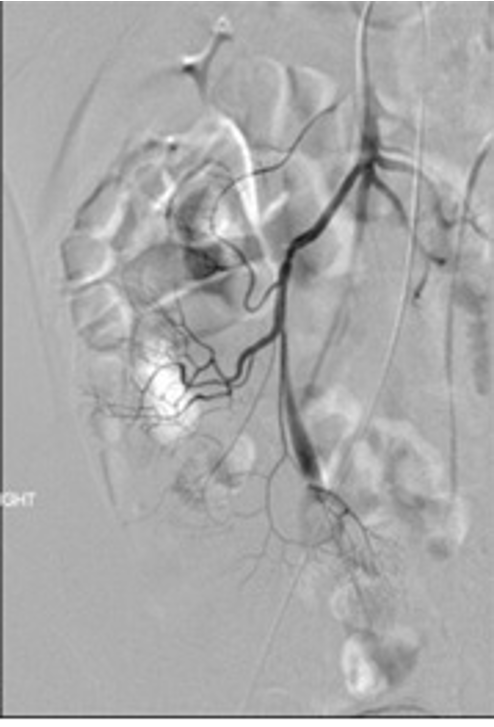

angiography shows a prominent vitelline artery

Meckel’s diverticula are a persistent outpouching due to periistent non involuting omphalomesenteric (vitelline) duct. 50% contain gastric mucosa